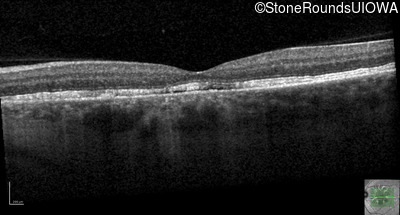

Optical Coherence Tomography - Left - 20/20

Exemplar / OCT Stack